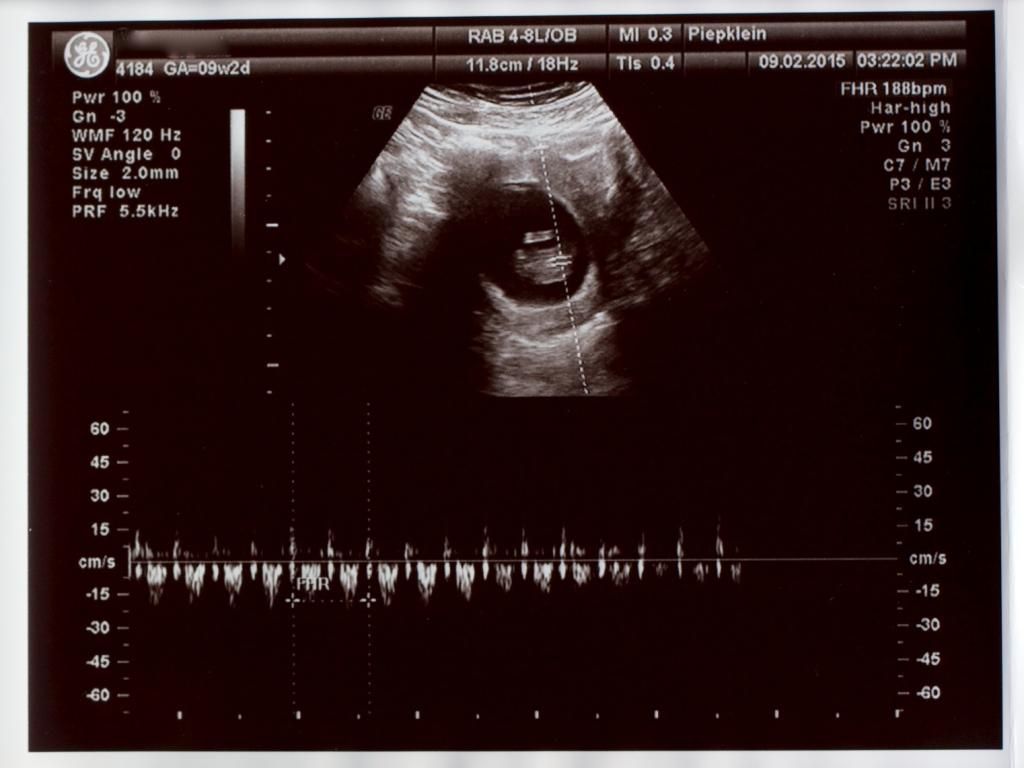

Wizzymaandag 23 februari 2015 @ 21:33

Vandaag voor de 2x een termijnecho gehad. De echoscopist was niet zeker van zijn zaak. Mijn baarmoeder is naar achteren gekanteld. Maar alle echo's lieten dezelfde termijn zien. Mijn uitgerekende datum mag naar 12-09-2015.

Nog gevraagd naar de nub-theorie maar dat vond hij maar een bakerpraatje -O- . Misschien kunnen jullie er wat uithalen. Al ligt hij/zij er niet goed voor.

Bij 9 weken

SPOILER

IMG_1172_zpsubeajnp8.jpg

IMG_1171_zpsqdkfjrn1.jpg

Bij 11 weken

IMG_1168_zps3f8bmibm.jpg

IMG_1166_zpsikkamaet.jpg

Tussendoor nog te horen gekregen dat de nekplooi niet verdikt is ^O^

Is nog iets te vroeg om de NUB vast te stellen, dat is tussen 12 en 14 weken. De NUB kan nog iets veranderen namelijk. Maar voor nu neig ik naar een jongen.

op beide foto's is geen nub te zien :) maar zoals eerder gezegd is het ook nog te vroeg voor nub. Overigens is nub gewoon wetenschappelijk bewezen, en zeker geen bakerpraatje. Alleen het is geen theorie die 100% zekerheid geeft over het geslacht.